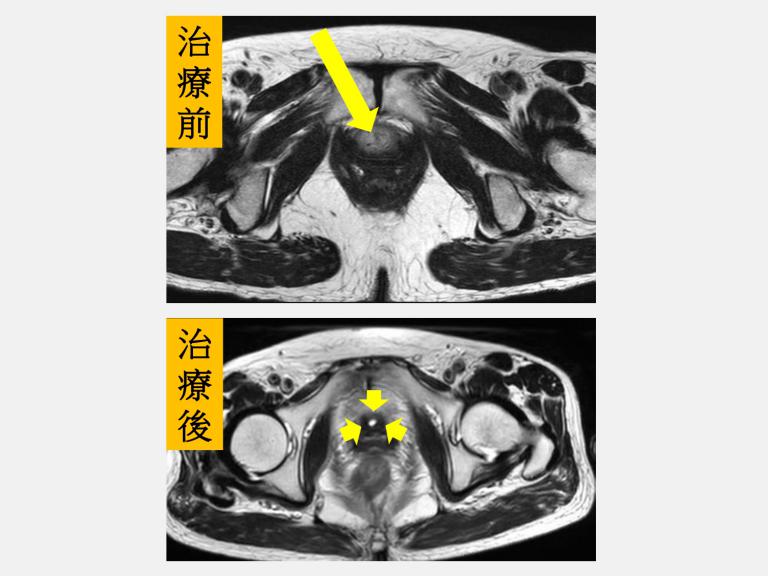

▲一名婦人長期性反覆小便疼痛、血尿及解尿困難,仁愛長庚醫院泌尿科劉緯陽主任檢查後發現她竟是罕見HPV導致的尿道鱗狀細胞癌,經化療及放療後尿道腫瘤已消失,目前仍接受積極追蹤中。(圖╱仁愛長庚醫院提供)

70多歲的李姓婦人因長期性反覆小便疼痛、血尿及解尿困難,到仁愛長庚合作聯盟醫院(大里仁愛醫院)泌尿科劉緯陽主任的門診求治,經施作內視鏡尿道腫瘤刮除,術後病理報告為罕見HPV(人類乳突病毒)導致的尿道鱗狀細胞癌。由於患者的尿道鱗狀細胞癌具侵犯性為第三期,經腫瘤團隊會議專家討論後,決定由時任血液腫瘤科江佳駿醫師安排化療,以及放射腫瘤科盧皓維主任同步安排放射治療。李姓婦人經過腫瘤團隊合作三個月治療後,尿道鏡追蹤及核磁共振掃描下發現尿道腫瘤已消失,目前仍接受積極追蹤中。

盧皓維主任表示,李婦腫瘤侵犯範圍廣泛,若直接進行手術切除,恐將影響正常泌尿道功能。經劉緯陽主任評估後轉介至放射腫瘤科,並會同血液腫瘤科共同規劃治療策略,爭取泌尿道器官保存的可能性。經跨科團隊充分討論後,最終決定採取根治性同步化學放射治療,以尿道腫瘤作為主要照射目標。由於病灶位置鄰近外陰部的敏感皮膚區域,李婦在治療期間一度出現中度以上的放射線皮膚炎及泌尿道發炎等副作用。然而,在醫療團隊細心照護,以及李婦耐心配合與高度信任下,仍順利完成完整療程。治療結束後,相關副作用都已恢復,後續追蹤檢查也顯示腫瘤已消失,治療成效良好。